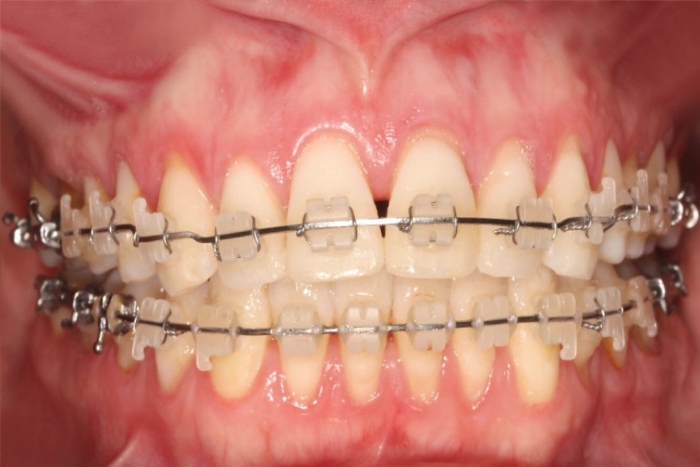

Mordida inicial